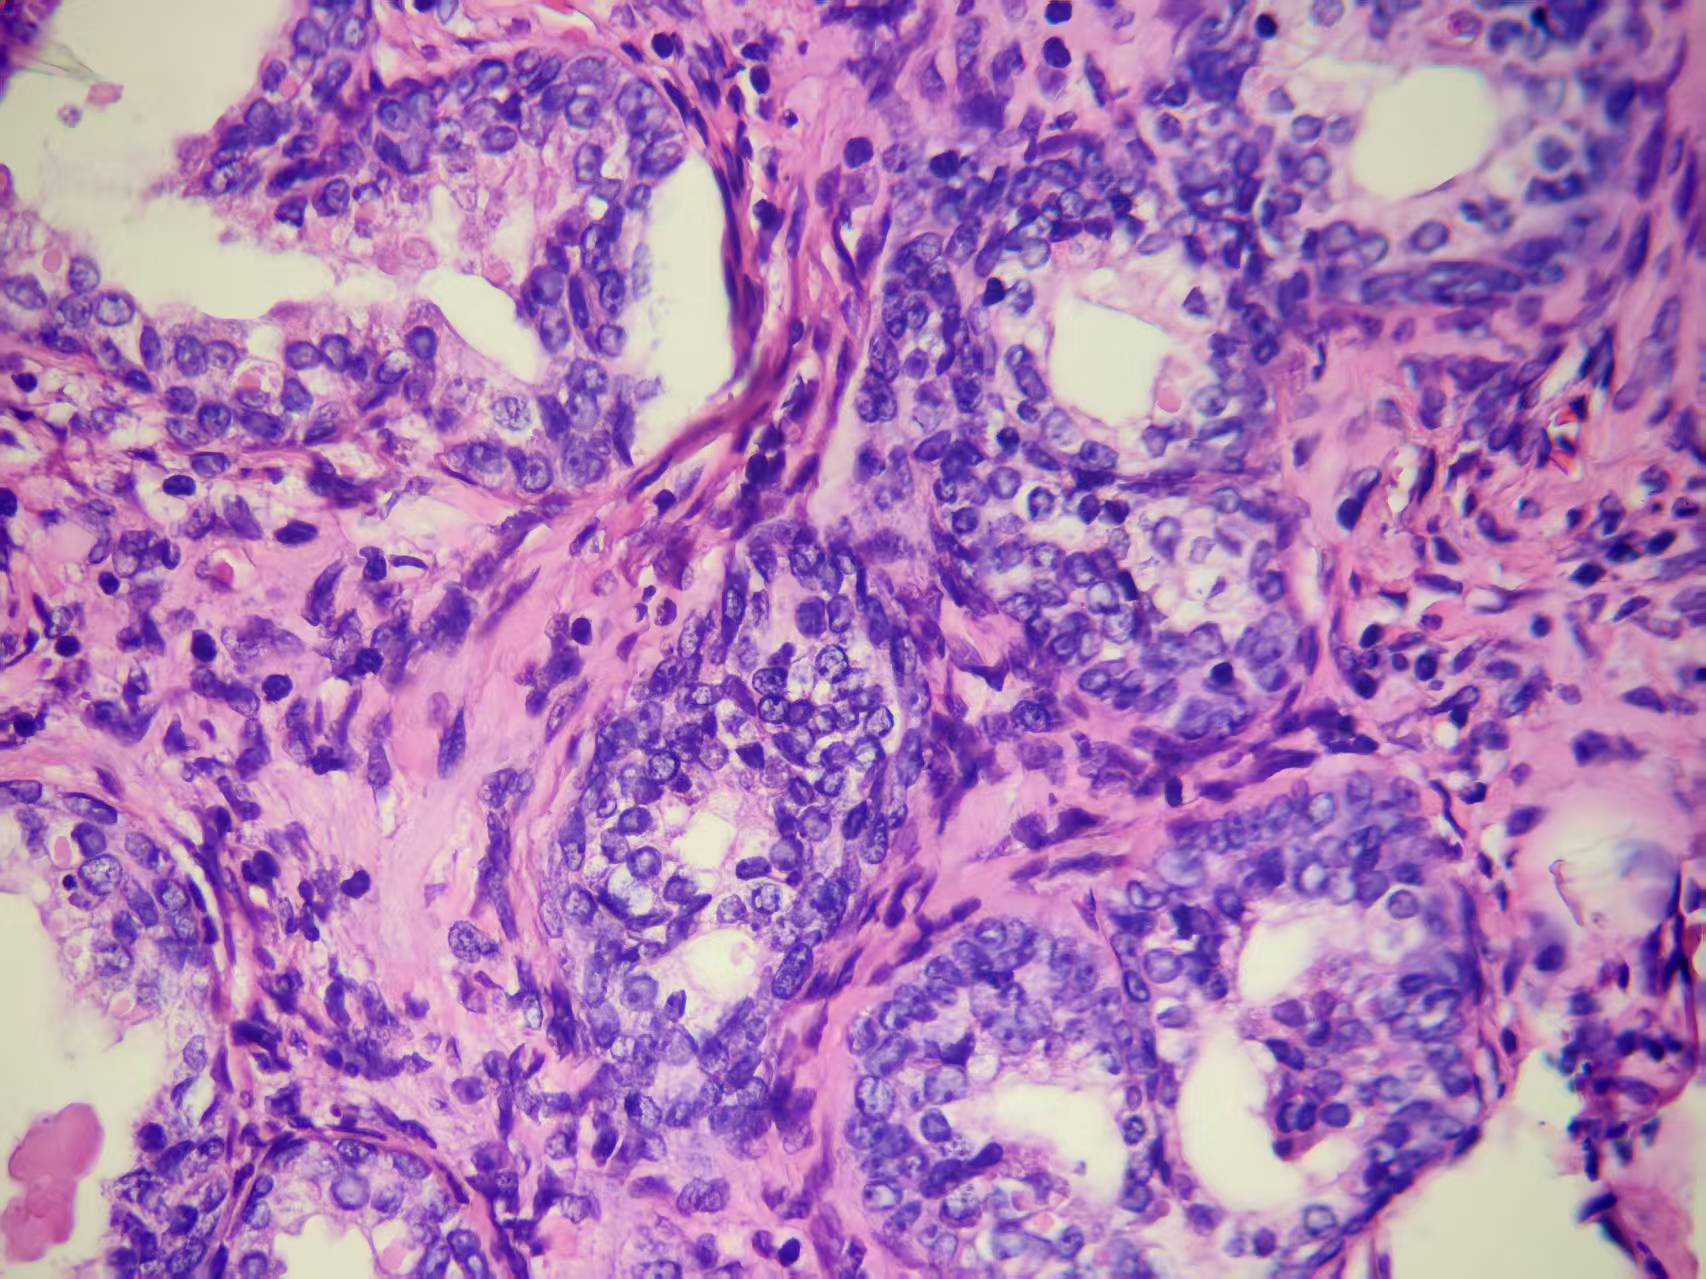

前列腺PIN?

发现肉眼血尿5月余,PAS 5.7

经尿道前列腺等离子电切组织

本例核仁巨大,值得关注!

嗜酸性大核仁,胞浆透亮,PIN没问题。还是组化一下吧,